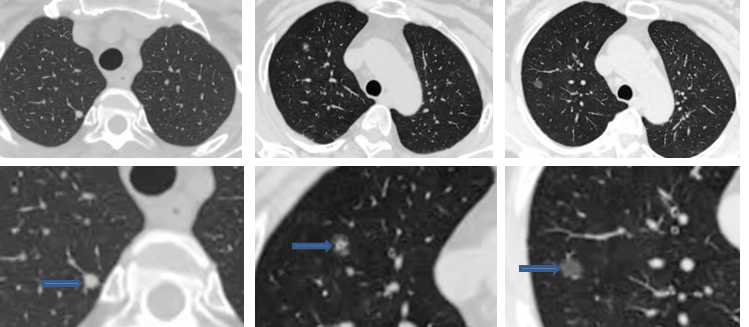

根据肺结节的密度分为:磨玻璃结节、实性结节,磨玻璃结节根据结节内部密度均匀程度又分为纯磨玻璃结节和混合磨玻璃结节。

实性结节 混合磨玻璃结节 磨玻璃结节